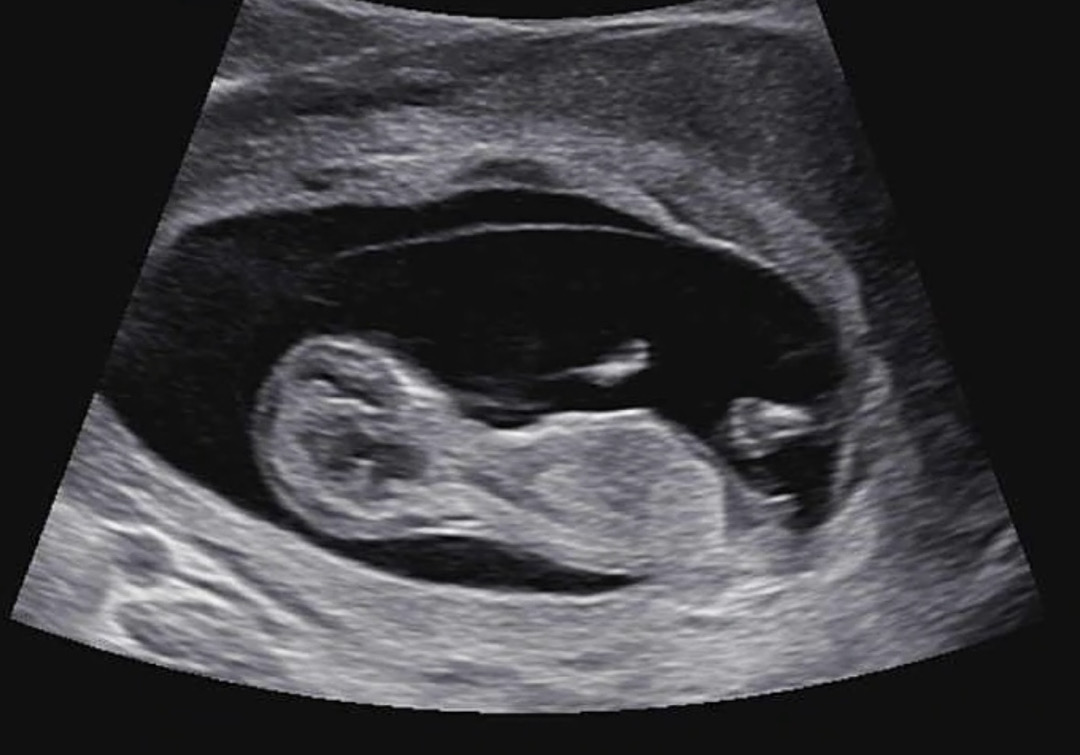

안녕하세요!! 각도법 고수님들 한번 봐주세요!!🥹

12주 1일 인데 기형아 검사하면서 촘파 검사도 봤는데 잘 모르겠어서 같이 봐주세요🥹😖 오늘 애기가 잘 움직이는거 보니까 떨리고 설레네요 !!!

손가락, 발가락도 보이네요~~! 너무 귀여워용! 기형아 검사하면 당일에 목 투명대도 같이 재주시나요오~??